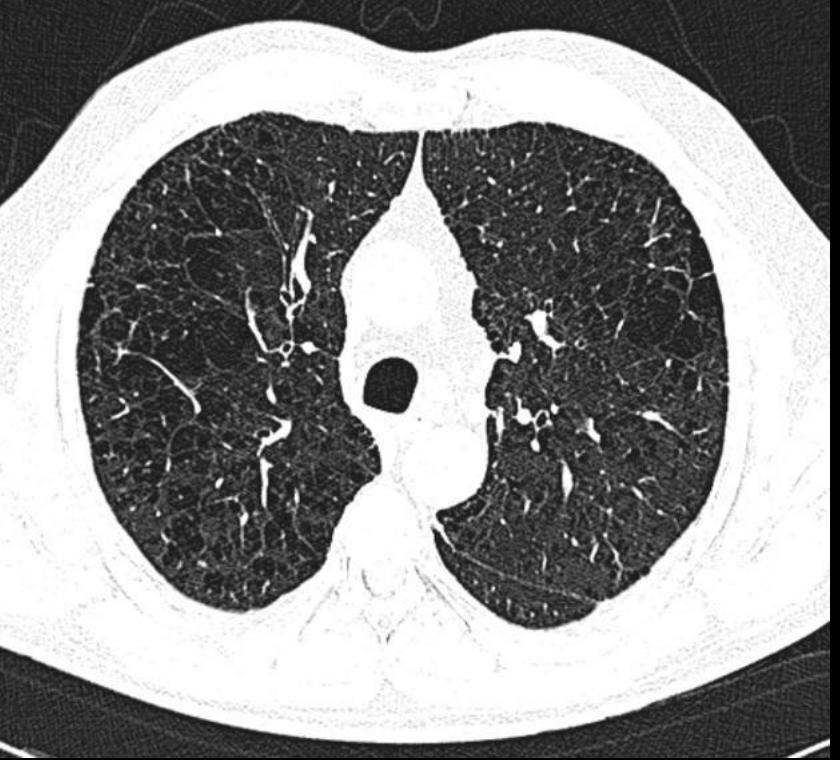

Signo del anillo en bronquitis crónica

Tranvias y anillos